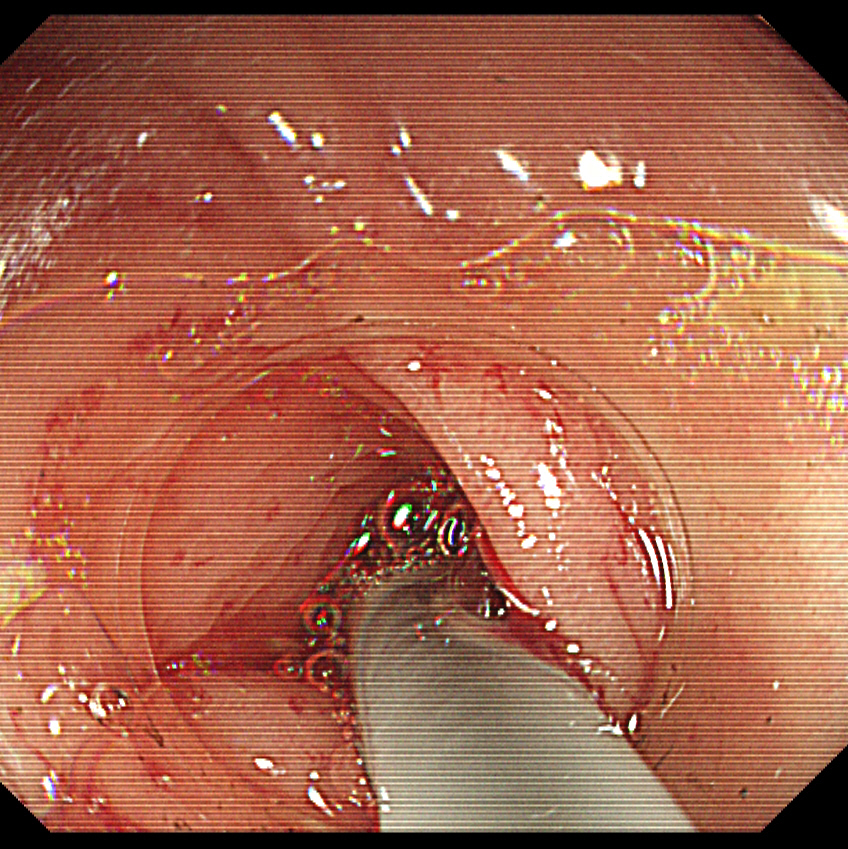

3、洞察系统察看粪石并套取

图片